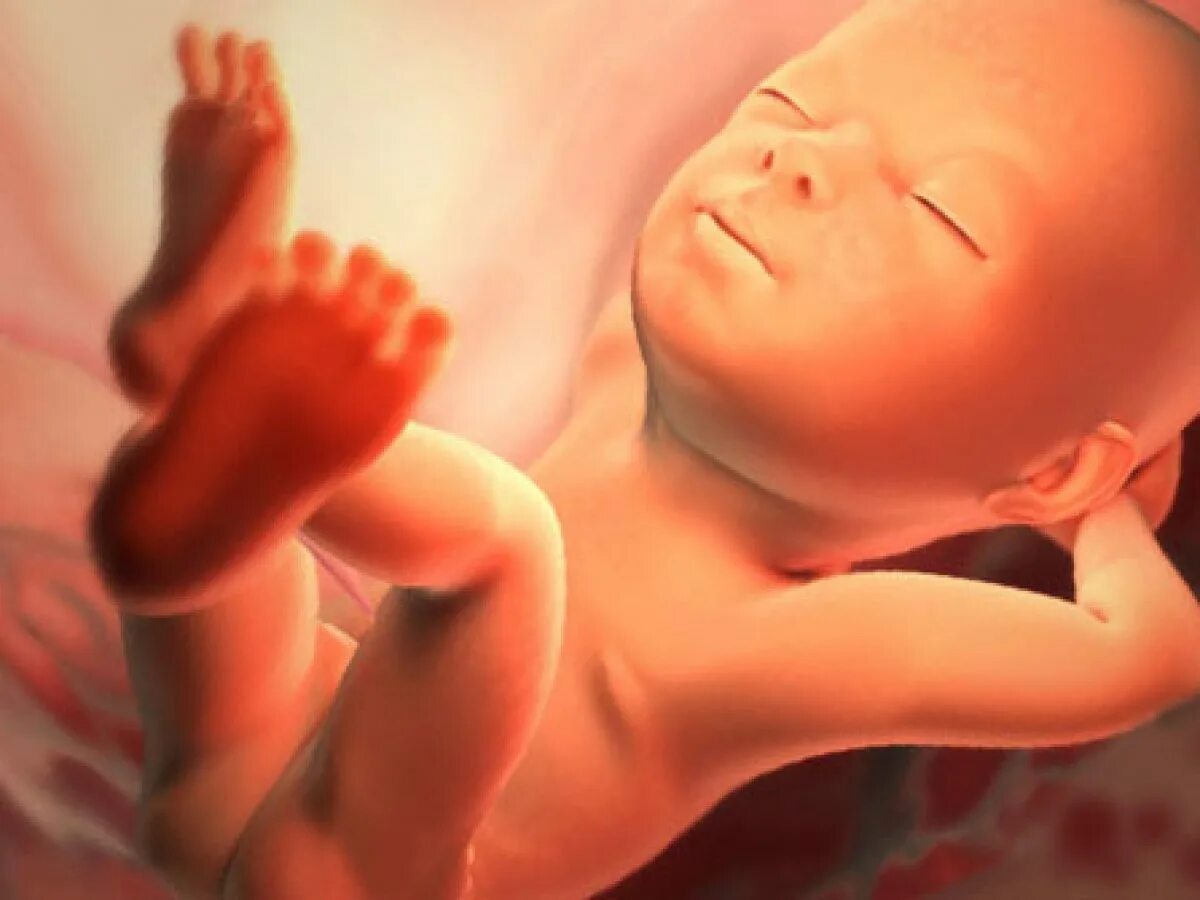

Как выглядит ребенок в 34 недели